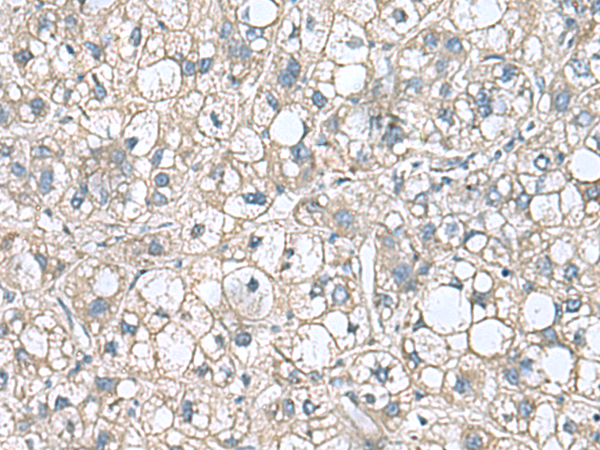

分类: 科研抗体货号: P10212别名: EDI3; GDE5; GDPD6; PREI4应用: WB,IHC反应种属: Human, Mouse, Rat